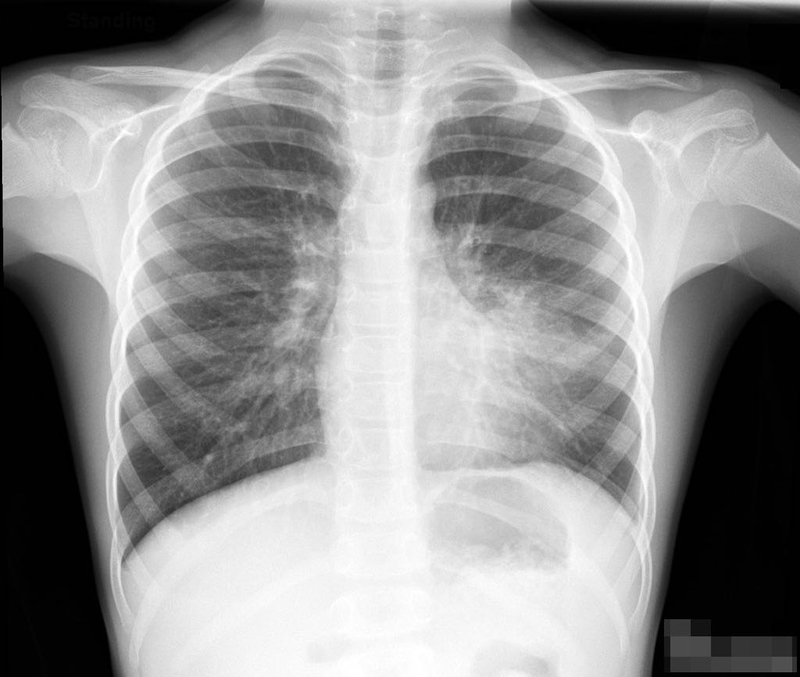

• Chụp X-quang ngực: Phương pháp này giúp chẩn đoán viêm phổi bằng cách tạo ra hình ảnh về tình trạng của nhu mô phổi. X-quang thường cho thấy các tổn thương như tình trạng tổn thương phế nang và mô kẽ phổi.

Cách lập kế hoạch chăm sóc bệnh nhân viêm phổi như thế nào? 3

Chụp X-quang ngực giúp hỗ trợ chuẩn đoán chính xác bệnh lý viêm phổi và đánh giá tổn thương phổi